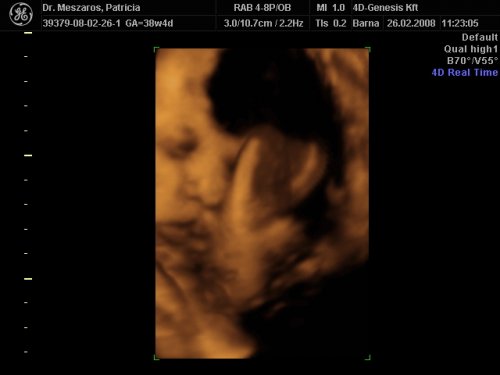

A doki szerint pufók kislány